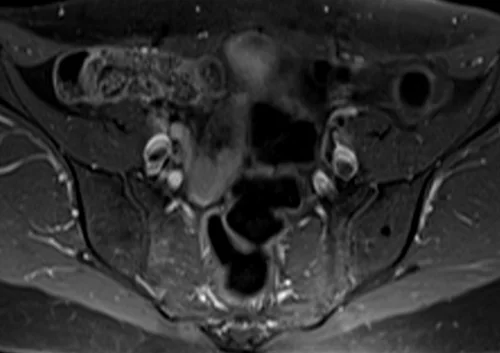

L plexus mri T1 fat saturated post contrast axial images